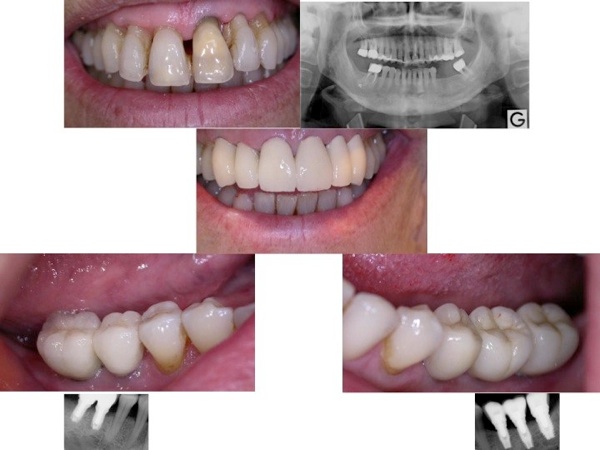

Parodontite = perte d’attache ( os , gencive, ligaments , cément radiculaire) , partiellement réversible par traitement non chirurgical ( détartrages et surfaçages radiculaires ) ou chirurgical et reprise correcte de l'hygiène dentaire et maintenance parodontale régulière . La perte osseuse horizontale est irréversible. On peut régénérer l’os partiellement dans le cas des lésions osseuses verticales.

2.Traitement Chirurgical - phase corrective :

- diminuer la profondeur de la poche parodontale , pour recréer des conditions favorables à une maintenance à long terme

A/-Méthode résective : l’élimination des poches , chirurgie osseuse

B/-Méthode d’assainissement parodontal : Lambeau de Widman modifié

C/-Méthodes régénératives ( RTG régénération tissulaire guidée )

-membrane RTG ( type Bio-Gide ) seule ou associé aux biomatériaux ( type Bio-Oss )

-permet une régénération osseuse et une nouvelle attache

Pour certaines dents il faut prendre la décision d’extraction et remplacement par des implants , avant que la résorption osseuse soit trop avancée.

1.attelle de contention ou bridges ( pour les dents mobiles )

2.couronnes pour refaire des papilles , en changeant la forme de la dent

5.implants pour remplacer les dents irrécupérables